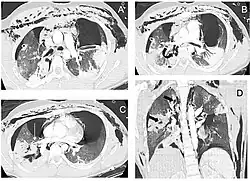

Chest x-ray is the initial imaging technique used to diagnose TBI.[17] The film may not have any signs in an otherwise asymptomatic patient.[15] Indications of TBI seen on radiographs include deformity in the trachea or a defect in the tracheal wall.[17] Radiography may also show cervical emphysema, air in the tissues of the neck.[2] X-rays may also show accompanying injuries and signs such as fractures and subcutaneous emphysema.[2] If subcutaneous emphysema occurs and the hyoid bone appears in an X-ray to be sitting unusually high in the throat, it may be an indication that the trachea has been severed.[4] TBI is also suspected if an endotracheal tube appears in an X-ray to be out of place, or if its cuff appears to be more full than normal or to protrude through a tear in the airway.[17] If a bronchus is torn all the way around, the lung may collapse outward toward the chest wall (rather than inward, as it usually does in pneumothorax) because it loses the attachment to the bronchus which normally holds it toward the center.[6] In a person lying face-up, the lung collapses toward the diaphragm and the back.[23] This sign, described in 1969, is called fallen lung sign and is pathognomonic of TBI (that is, it is diagnostic for TBI because it does not occur in other conditions); however it occurs only rarely.[6] In as many as one in five cases, people with blunt trauma and TBI have no signs of the injury on chest X-ray.[23] CT scanning detects over 90% of TBI resulting from blunt trauma,[3] but neither X-ray nor CT are a replacement for bronchoscopy.[6]